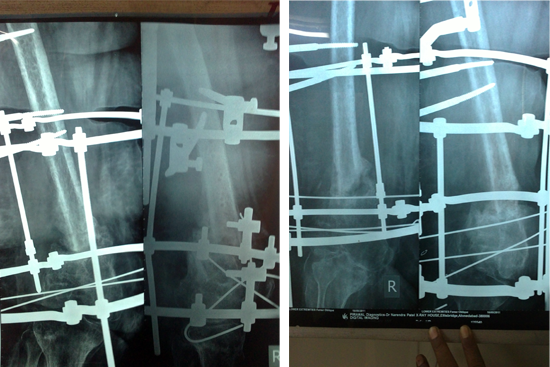

Non Union Femur

Case 1

Case 2 (Rampyari)